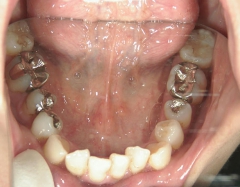

矯正歯科 治療後矯正歯科 全顎ワイヤー矯正 治療後矯正歯科(全顎ワイヤー矯正)治療後

治療期間2年6ヶ月

矯正_灰色.pngno.7_6967_治療後_下_01.jpg矯正_灰色.png